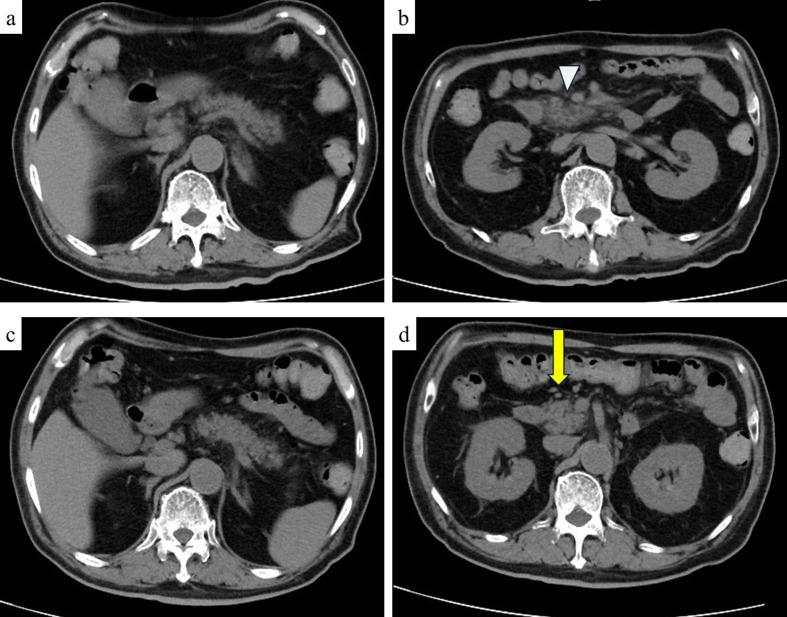

Since the onset of the coronavirus disease 2019 (COVID-19) pandemic, COVID-19 vaccination has substantially reduced mortality and hospitalization rates worldwide, with rare adverse events reported in clinical settings. Herein, we present a case of acute pancreatitis complicated by diabetic ketoacidosis (DKA) following the third COVID-19 vaccination dose. A 72-year-old male with a history of diabetes mellitus developed generalized fatigue, mild epigastric pain, nausea, and frequent vomiting after receiving the COVID-19 vaccine. Blood analysis revealed elevated levels of pancreatic enzymes, hyperglycemia, and acidemia. Computed tomography revealed evidence of acute pancreatitis, leading to a diagnosis of both DKA and acute pancreatitis. Treatment with a large volume of saline and intravenous insulin improved both DKA and acute pancreatitis. After a thorough examination, no other factors capable of causing acute pancreatitis were identified. Hence, we concluded that acute pancreatitis was induced by COVID-19 vaccination. Acute pancreatitis is a rare but potentially life-threatening adverse event associated with COVID-19 vaccination. Delaying the treatment or diagnosis of acute pancreatitis can increase mortality risk in patients with both acute pancreatitis and DKA. Hence, it is crucial for healthcare professionals to consider the potential occurrence of acute pancreatitis and DKA following COVID-19 vaccination.

自2019年冠状病毒病(COVID-19)大流行开始以来,COVID-19疫苗接种已大幅降低了全球的死亡率和住院率,临床环境中报告的不良事件很少。在此,我们报告一例在接种第三剂COVID-19疫苗后并发糖尿病酮症酸中毒(DKA)的急性胰腺炎病例。一名有糖尿病病史的72岁男性在接种COVID-19疫苗后出现全身乏力、轻度上腹部疼痛、恶心和频繁呕吐。血液分析显示胰酶水平升高、高血糖和酸血症。计算机断层扫描显示有急性胰腺炎的迹象,从而诊断为DKA和急性胰腺炎。大量生理盐水和静脉注射胰岛素治疗改善了DKA和急性胰腺炎。经过全面检查,未发现其他能够引起急性胰腺炎的因素。因此,我们得出结论,急性胰腺炎是由COVID-19疫苗接种引起的。急性胰腺炎是一种与COVID-19疫苗接种相关的罕见但可能危及生命的不良事件。延迟急性胰腺炎的治疗或诊断会增加急性胰腺炎和DKA患者的死亡风险。因此,医护人员考虑COVID-19疫苗接种后急性胰腺炎和DKA的潜在发生情况至关重要。